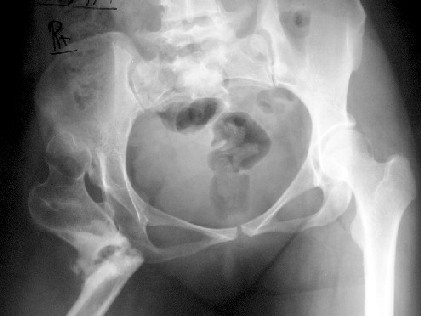

A 30-year-old female patient, presented with pain and limping post hip surgery and lengthening using Ilizarov technique 2 years duration.She said she had only limping preop. now she has painful limping and she can't walk without using walking aid.

Her X-ray --> non-union at the osteotomy site,pelvic tilt,bowing of the femur. clinically painful mobile pseudoarthrosis, LLD =4CM. Could those colleagues using such type of osteotomy Ilizarov method give us the clues how to treat such problems? Does this type of osteotomy still practiced by the group? Dr.Freih Odeh Abu Hassan, M.D(Orth.), F.R.C.S(Eng.), F.R.C.S.(Tr.&Orth.), Asst.Professor of Orthopedics Surgery, Jordan University - Amman.